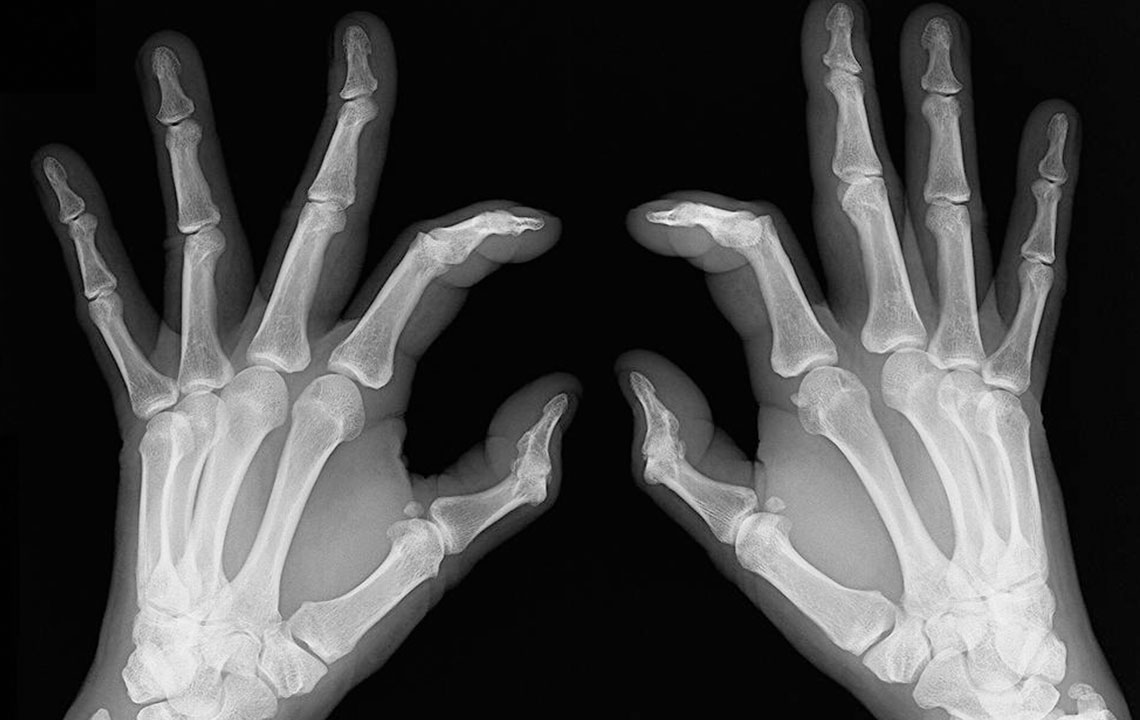

- Bone deformation: Arthritis also attacks the bones and makes them crooked and stiff. Look out for signs of any subtle changes in your joints and test them for pain levels.

Rheumatoid arthritis causes chronic inflammation of joints, which results in joint pains, inflammation and bone deformation. It usually starts slowly with pain in some parts of the body that can come and go in the beginning and then spread within weeks or months. It is better in this day and age to always be aware of your health problems and not to ignore slightest of joint pains. The symptoms can vary from one person to another.

- Inflammation: Sometimes rheumatoid arthritis symptoms show chronic flare up and can lead to swollen joints and inflammation. They are also symptomatic of lupus, so do consult your doctor before getting yourself treated for rheumatoid arthritis.